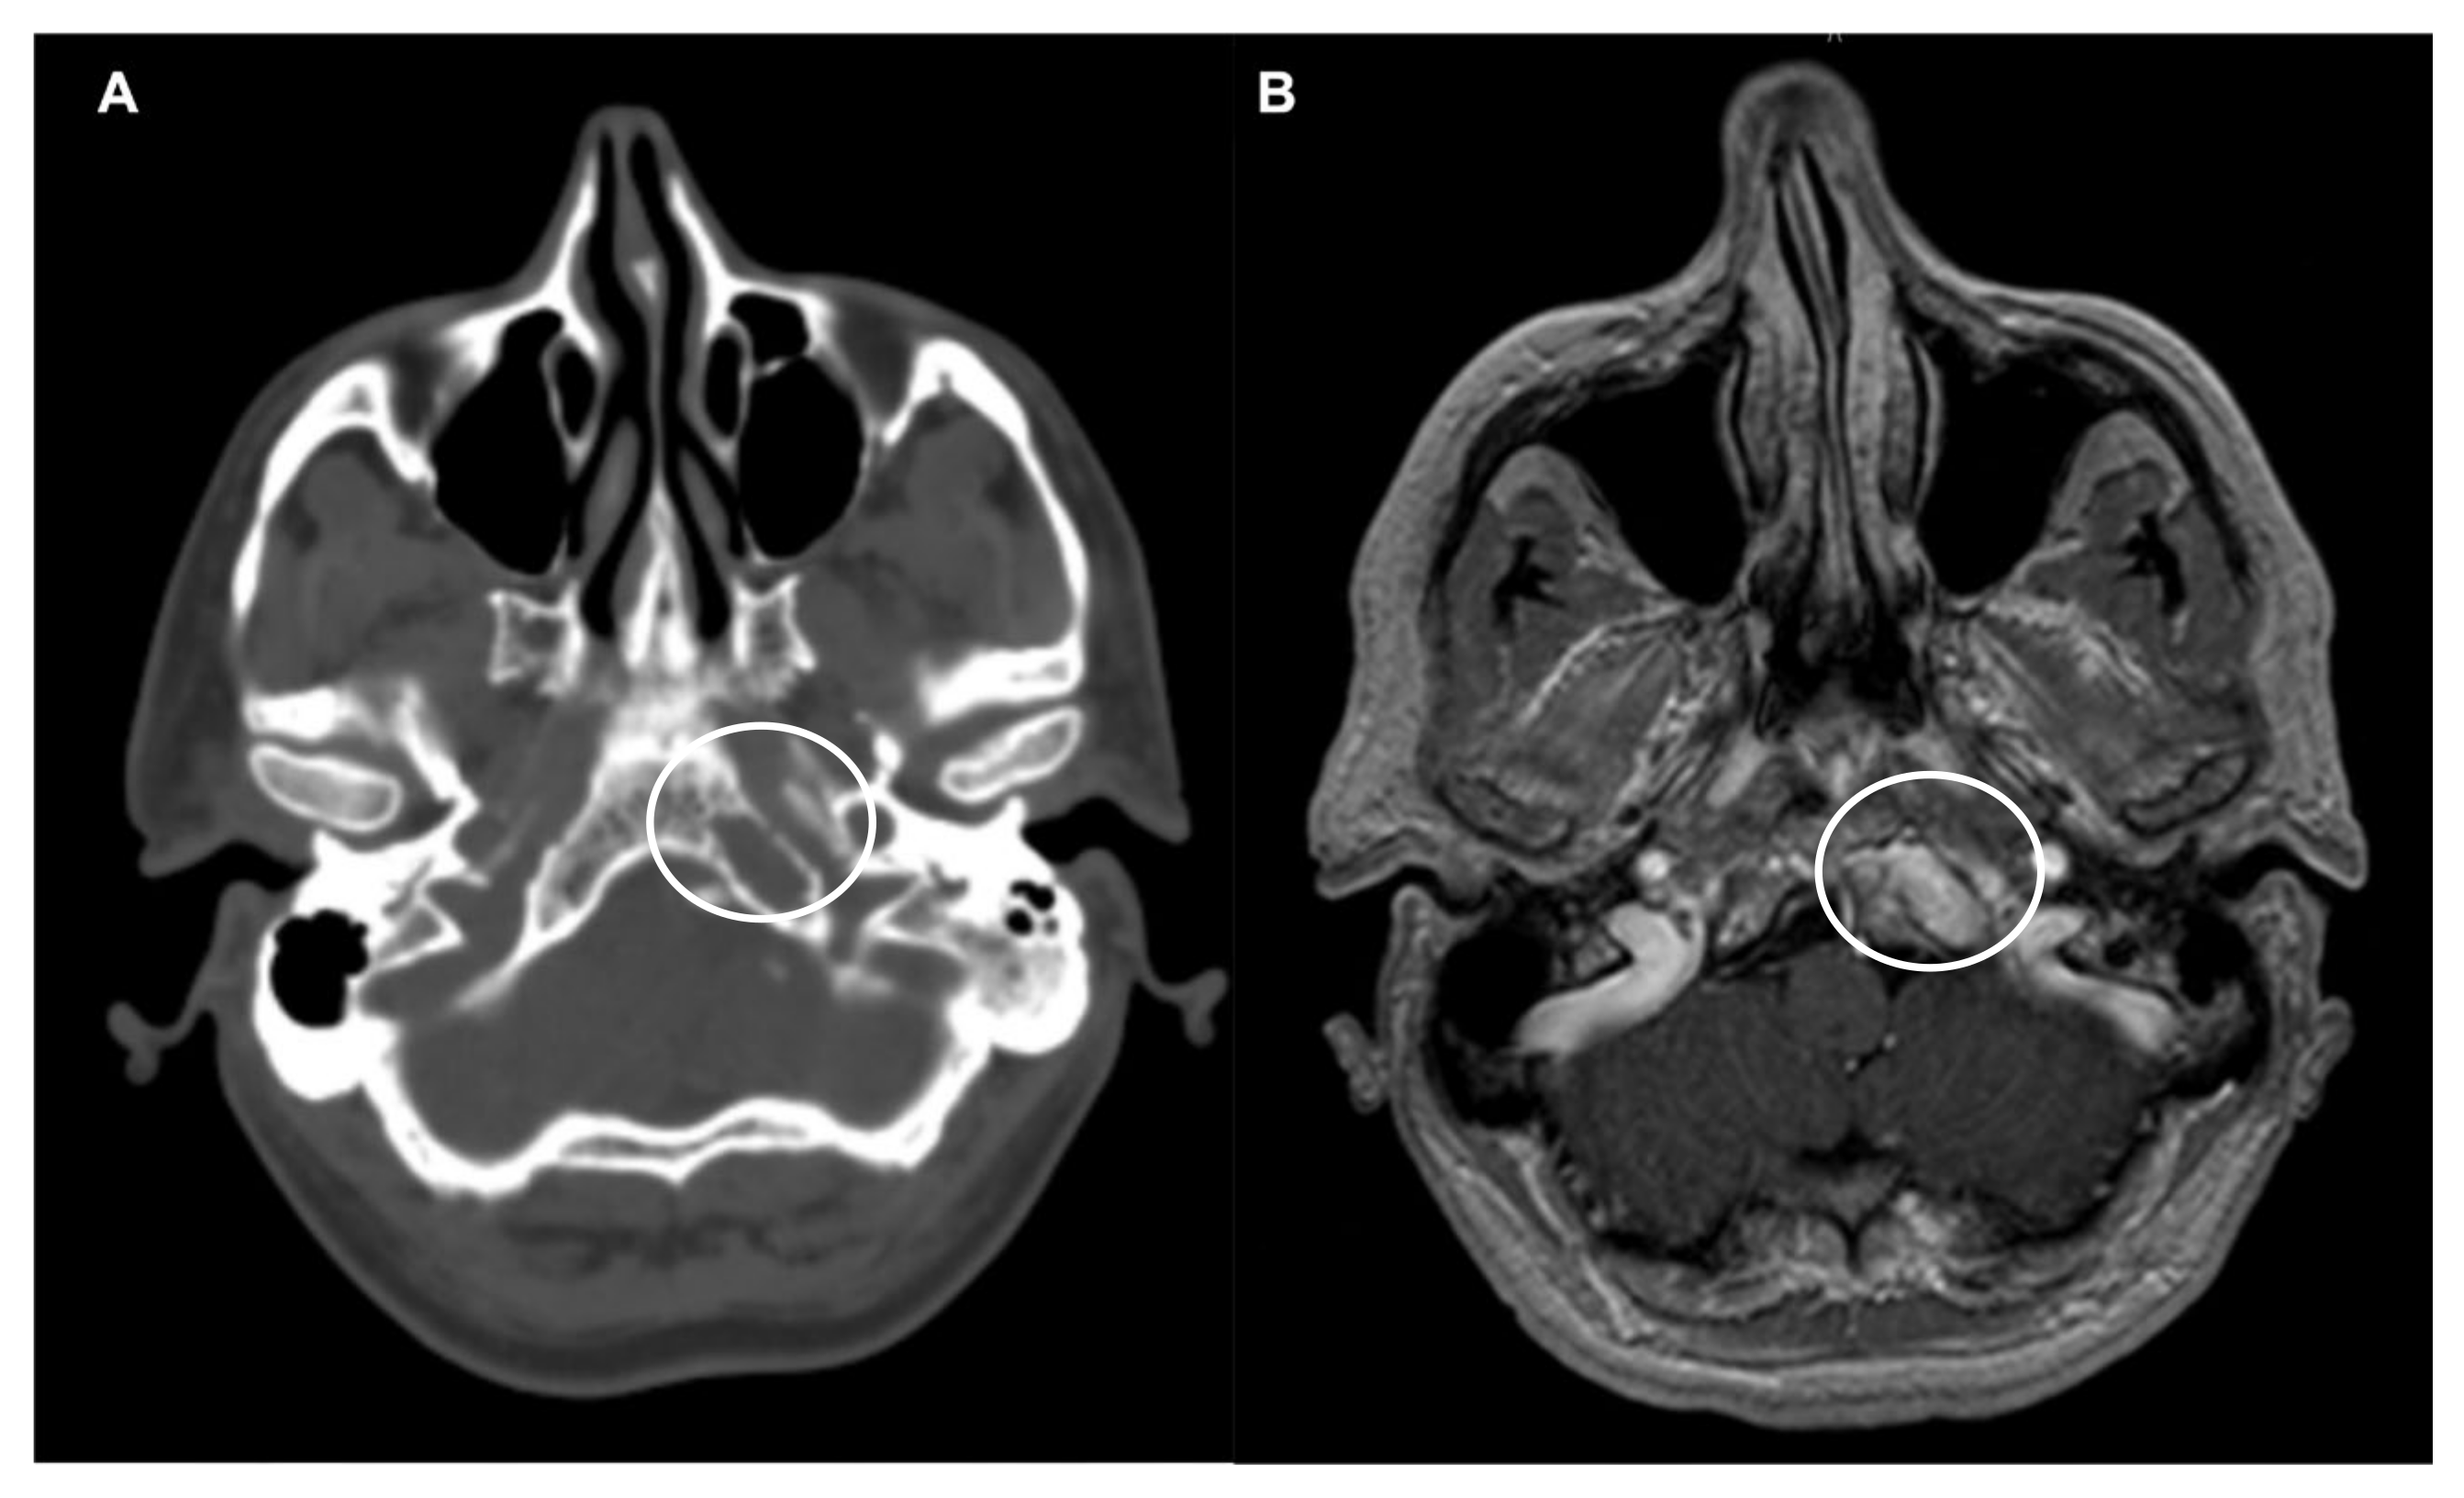

Figure 2.

Lower clivus solitary plasmacytoma. (A) Axial CT scan showing a lytic expansile lesion at the left lower clivus (circle). (B) Axial T1-weighted after contrast injection image showing a heterogenous and hyperintense lesion (circle). A minimally invasive endoscopic endonasal biopsy disclosed the plasmacytoma.